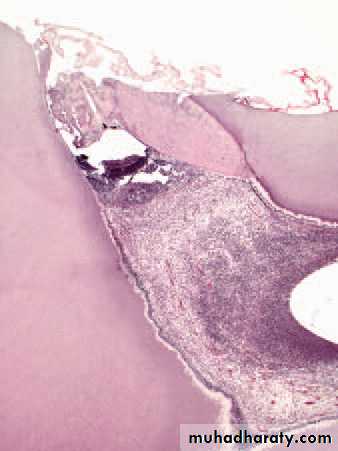

Traumatic exposure. The pulp has been exposed during cavity preparation.

Cracked tooth. The pulp died beneath this crack which was undetectedclinically but which has opened up after decalcifi cation of the tooth.